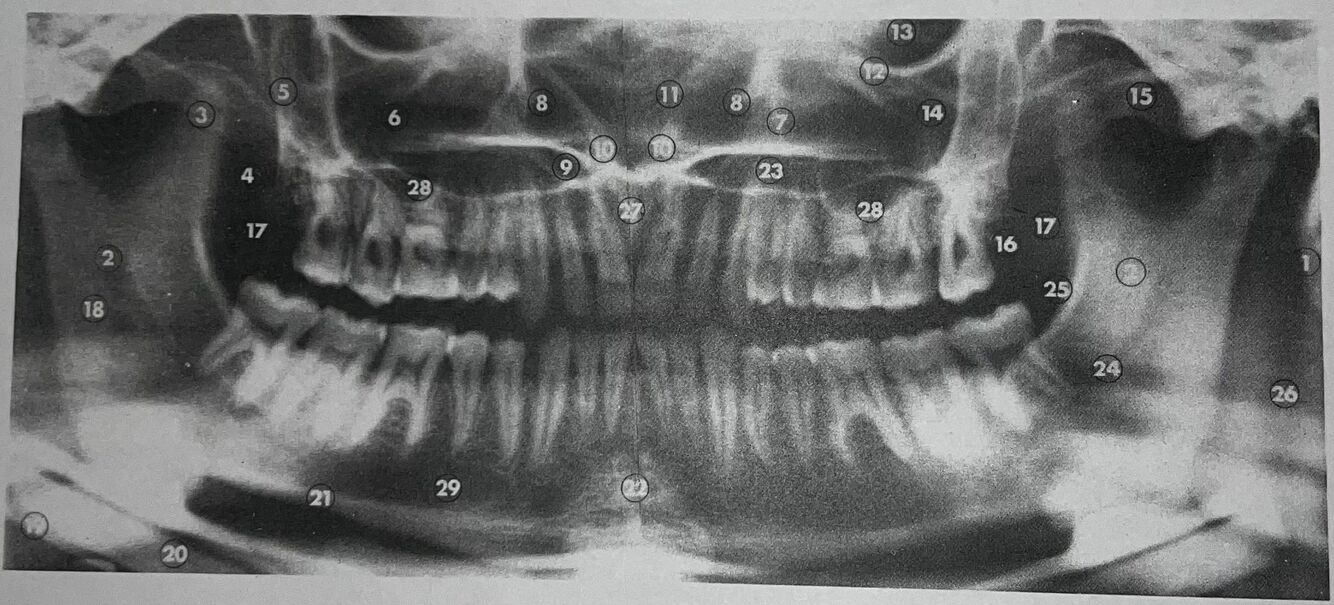

what is 1

mastoid process

what is 2

what is 3

coronoid process

what is 4

lateral pterygoid plate

what is 5

posterior wall of antrum

what is 6

antrum (maxillary sinus)

what is 7

anteromedial wall of antrum

what is 8

inferior concha

what is 9

floor of nasal fossa

what is 10

anterior nasal spine

what is 11

nasal septum

what is 12

infraorbital ridge

what is 13

orbital cavity

what is 14

malar process

what is 15

zygomatic arch

what is 16

maxillary tuberosity

Q

what is 17

what is 18

what is 20

inferior border of mandible

what is 22

mental protuberance

what is 23

23

what is 24

mandibular canal

what is 25

internal oblique line

what is 26

superimposition of right jaw

what is 27

incisive canals

what is 28

floor of antrum

what is 29

mental foramen